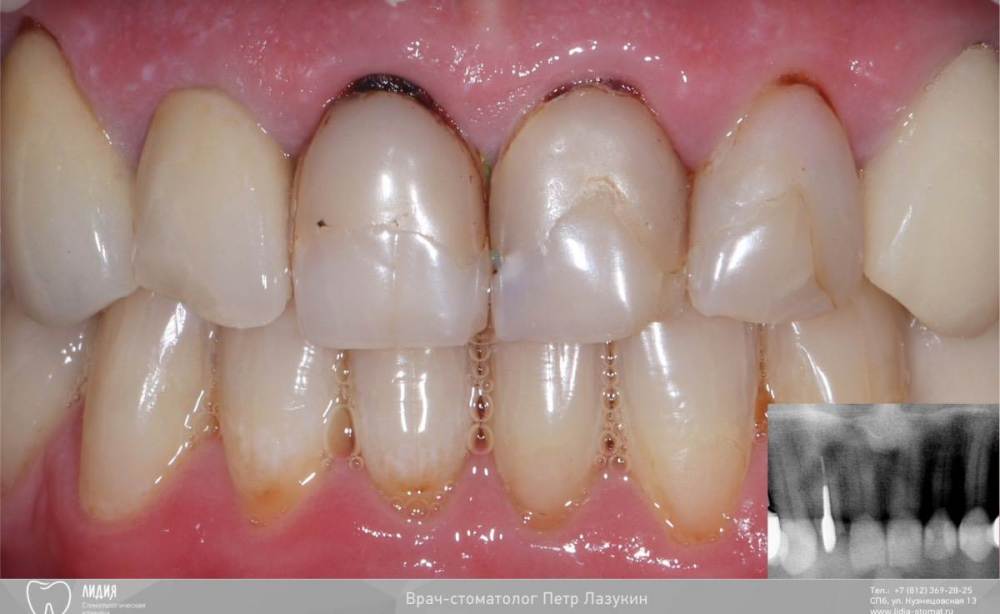

Всем привет! Кейс. Изготовление 4-х коронок из диоксида циркония. Этапы работы: воск, примерка макета, препарирование, восстановление культей, временные коронки. Перерыв в 2 недели. Оценка витальности зубов. Оттиски, фиксация коронок. Коррекция зенита 12 зуба улучшила бы результат, но пациент отказался1530444424__001.thumb.jpeg.3fe86d2d496d1938fdb93c4c8936392a.jpeg979574669__002.thumb.jpeg.c922494ff1f98ef4ab45f5b831a5139c.jpeg1100820898__003.thumb.jpeg.b1d8cfdff23d97d0069e63c41d83ef02.jpeg1238733524__004.thumb.jpeg.3f1fabfb042f99f6dfc2376bae98da61.jpeg114595588__005.thumb.jpeg.b1c9a5d10b6f0a8f7af94d82590ef602.jpeg1347437548__006.thumb.jpeg.42b29c11f9dfaa62ab6e6184263019e5.jpeg809667846__007.thumb.jpeg.6184075490de758a248d4abff89cfab1.jpeg69728675__008.thumb.jpeg.12d9715618053c84cd4ce6e70a47191f.jpeg

1. Ретракция десны и глубокий преп, устранение воспаления десны за счет удаления кариеса и нависающих краев пломб

2. Да

3. через 3-6 месяцев

3. ничего. Просто оставляю место на коронках